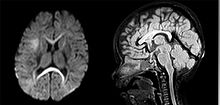

| An MRI of a patient with benign familial macrocephaly (male with head circumference > 60cm) | |

Macrocephaly is a condition in which the human head is abnormally large; this includes the scalp, the cranial bone, and the contents of the cranium. It may be pathological or benign, even a familial genetic characteristic. People diagnosed with macrocephaly will have further testing done to determine whether the syndrome is accompanied by any other disorders. Those with benign or familial macrocephaly are considered to have megalencephaly, another form of macrocephaly that will not result in the development of neurological disorders in the patient.

Many people with abnormally large heads or large skulls are healthy, but macrocephaly may be pathological. Pathologic macrocephaly may be due to megalencephaly (enlarged brain), hydrocephalus (abnormally increased cerebrospinal fluid), cranial hyperostosis (bone overgrowth), and other conditions. Pathologic macrocephaly is called "syndromic", when it is associated with any other noteworthy condition, and "nonsyndromic" otherwise. Pathologic macrocephaly may be caused by congenital anatomic abnormalities, genetic conditions, or by environmental events.[1]